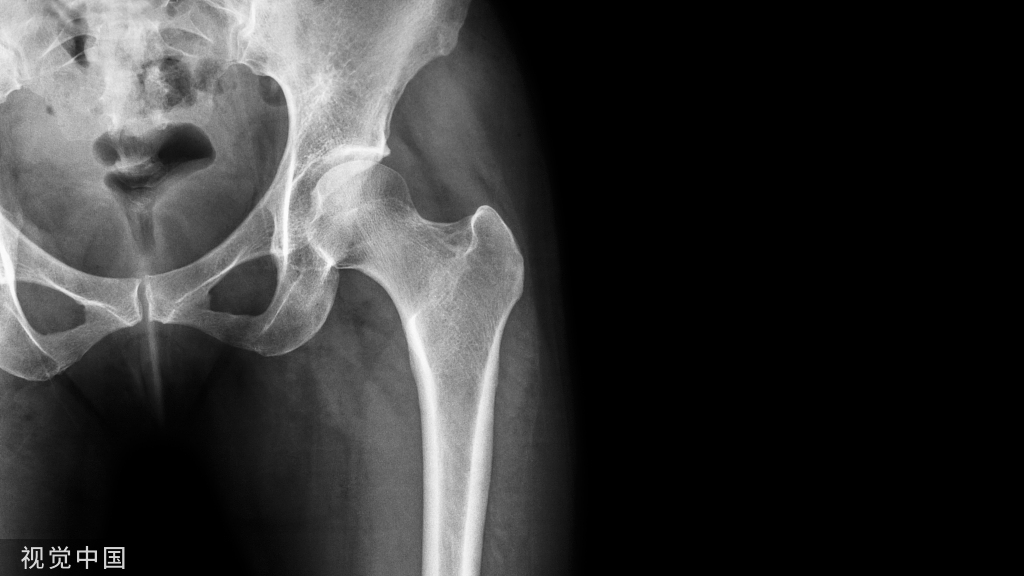

05股骨近端骨折

股骨颈骨折常发生在老年人,头下型骨折最常见,但是当股骨外旋或有明显的关节炎骨赘形成时,骨折较难发现。此外,肥胖和骨量减少增加髋部 X 片诊断难度,所以需格外注意。

因骨结构重叠影响,股骨转子骨折发生轻度移位时亦很难发现,加做一个不同角度的 X 线片有助于诊断(图 7)。

图 7 摔倒后股骨大转子骨折。A 正位片初步检查未发现明显骨折,进一步检查发现大转子上方皮质中断(箭头)。B 蛙式侧位片示骨折分离,尤其是后方(箭头)。初步检查时忽视了这一点,是因为股骨颈未能充分显